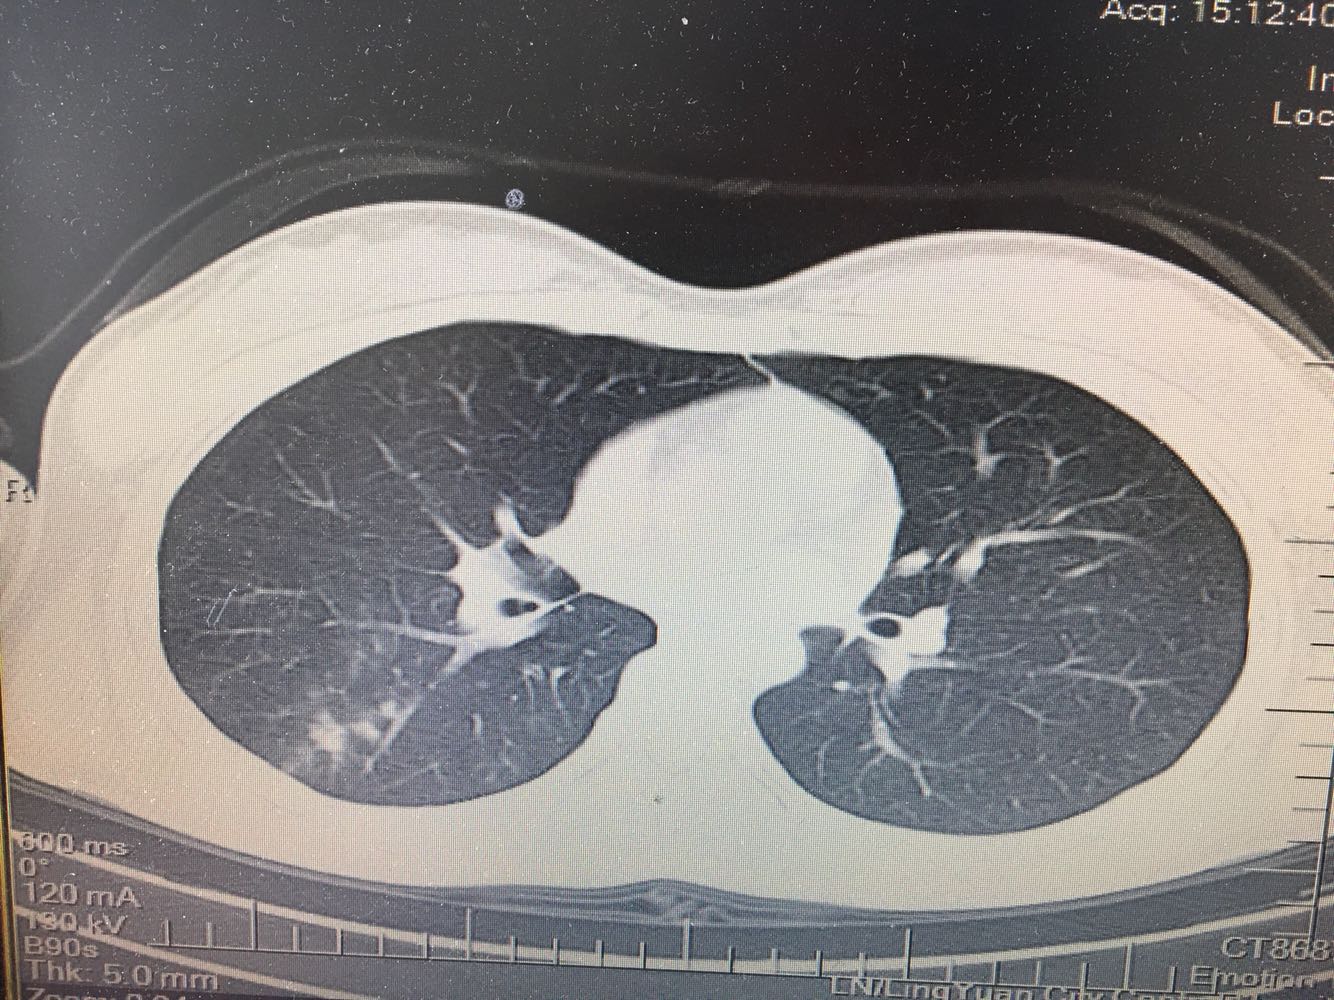

支原体肺炎?肺结核?

女,26岁,咳嗽1周,咳痰不畅,咽喉痒,口服阿莫西林无好转,昨日发热,体温38.5摄氏度,于门诊查肺CT后以肺炎收入院,病来无盗汗,无咳血,无消瘦及乏力,无头痛,无肢体酸痛,饮食睡眠可,二便正常

支原体抗体1:160,结核抗体弱阳性。支原体肺炎个别可见上叶病变,该患无结核中毒症状,考虑支原体肺炎可能性大,但肺尖为结核好发部位,需要抗炎治疗后复查观察疗效。